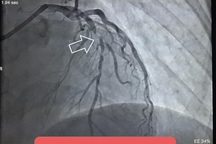

Loại thuốc nam sản phụ uống trước khi nhập viện cấp cứu (Ảnh: BV).